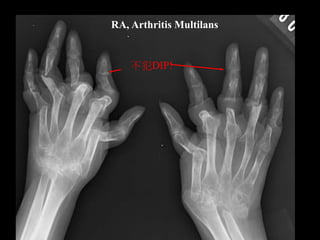

X-ray

比較一下!

Normal joint

RA patient

Margin erosion,吃進去

Boutonniere

fusion

RA, Arthritis Multilans

不犯DIP!